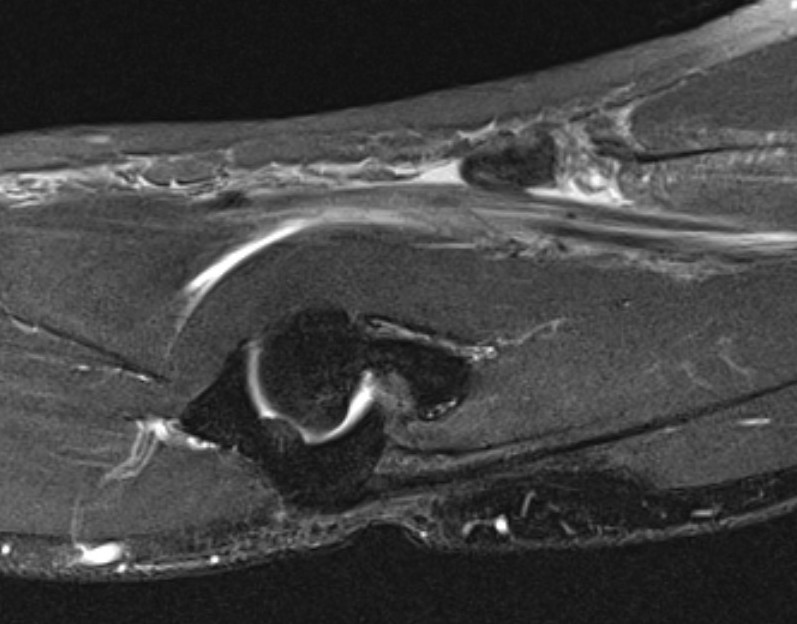

A.  Complete tear / retracted

Best seen on sagittal MRI

Distal biceps rupture MRIDistal biceps rupture MRI

Sagittal MRI - distal biceps retracted into arm

Distal Biceps Rupture MRI